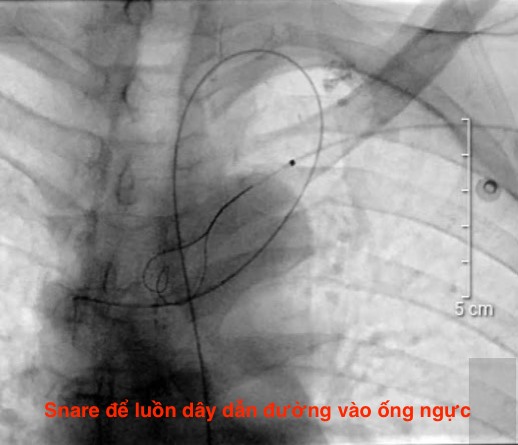

Một bệnh nhân của chúng tôi bị đái dưỡng chấp, có ứ trệ tuần hoàn ống ngực, chúng tôi đã luồn dây dẫn vào ống ngực để đi xuống tĩnh mạch chủ. Một đường khác từ tĩnh mạch cánh tay đưa thòng lọng vào để kéo dây dẫn. Bằng cách đó dùng bóng để nong điểm nối thông ống ngực và tĩnh mạch dưới đòn. Sau can thiệp, kết hợp với chế độ ăn giảm mỡ thì nước tiểu trong về bình thường.